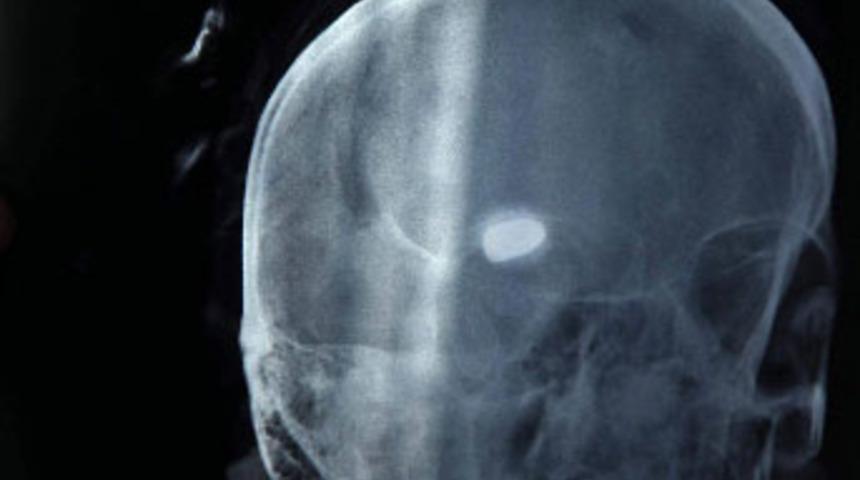

Gaziantep'te yaklaşık 3 ay önce akraba ziyareti için gittiği mahallede hamur yoğururken nerden geldiği belirlenemeyen mermi ile başından vurulan 50 yaşındaki Hüsne Bakıcı, felç oldu. Bakıcı'nın beynindeki mermi hayati tehlikeye neden olduğu için çıkarılamayınca, polis soruşturmayı bir türlü derinleştiremedi. Yetkililer, Bakıcı'nın ölümünen sonra başından çıkarılacak olan mermiden yola çıkılarak magandanın belirlenebileceğini söyledi.

Olay, 3 ay önce Güzelvadi Mahallesi'nde meydana geldi. Burada annesini ziyarete gelen Hüsne Bakıcı (50), bahçede ekmek yaparken biranda yere yığılmış ve hastaneye kaldırılınca çekilen röntgende beyninde mermi olduğu anlaşılmıştı. 25 Aralık Devlet Hastanesi'ne kaldırılan ve eşi 4 yıl önce vefat eden talihsiz kadın yoğun bakımda bir süre kaldıktan sonra hayati tehlikeyi atlattı. Bu sırada soruşturmayı Cumhuriyet Savcısı'nın talimatıyla sürdüren polis, doktorların bütün uğraşlarına rağmen kadının beyninden çıkaramadığı mermi yüzünden bir türlü ilerleme kaydedemiyor.

Bölgede inceleme yapan ve aynı zamanda birçok kişinin ifadesine başvuran polis, herhangi bir bulguya rastlayamadı. Hayati tehlikesi nedeniyle beyinden çıkarılamayan mermi ile felç kalan ve hafıza kaybına uğrayan Hüsne Bakıcı bu mermiyle yaşayacak. Polis çıkarılacak olan mermiden yola çıkarak, olayda kullanılan silahı ve daha sonra olayı gerçekleştiren magandaya ulaşmayı hedefliyor.

Bakıcı'nın doktorları, hastanın bilinç kaybı olarak geldiğini başındaki kanda beyin dokularını görününce kurşun olduğunu tahmin ederek film çektirdiklerini ve sol tarafından giren kurşunun 9 santimetre içeride olduğunu tespit ettiklerini söyledi.